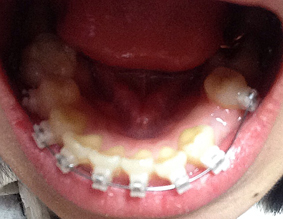

오늘 진행한 하악의 치아교정 장치는 클리피시교정으로

1차적으로 치아교정을 하는사람의 치아 모형을 기준으로 치아교정 장치를 제작,배치 시킨후

그것을 틀에 맞춰서 실제 치아에 달기때문에 부착 정확도가 더욱 크다고 해요

저는 치아교정 장치 달 때 마취도 하고 엄청 알거라고 생각했는데 마취 없이 진행하였는데도 하나도 아프지 않고 금방금방 진행되더라구요

치아교정 장치를 부착후 상악에 바이트블럭 이라는것을 부착하였어요. 이것은 맞물림을 덜 되게 하는것인데 말인 즉슨. 원래 제가 입을 다물면 앞니와 아랫니가 많이 겹쳐지는 맞물림이깊은 교합인데 교정기를 달은채로 그대로 다물게 되면 앞니의 뒤쪽과 교정기기 충돌하기 때문에 이것을 방지하기 위한 장치가 바이트블럭이라고 할 수있어요~

상학의 어금니쪽에 딱딱한 블럭을 덧대어 치아가 완전히 맞물리지 않게 하여 치아와 교정기의 충돌을 막아 줍니다

사진을 보면 상악 위쪽에 파란색 부분이 보이시나요? 이것이 바이트블럭 이에요~